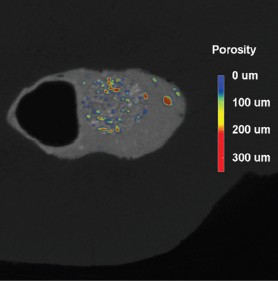

The X4 POSEIDON modular micro-CT system is equipped with a high resolution sCMOS detector that is ideal for examination of the microstructural integrity of teeth and dental restorations (Figures 2, 3 and 4). The X4 produces high-quality images from the outer to innermost structure of the tooth. In restorative dentistry, a key application is the study of the marginal and internal fit of filling materials, where research shows that the material type significantly influences the adaptability of the restoration, with some materials achieving lower marginal and internal gap values.

Voids, gaps, and bubbles can reduce the mechanical properties of resin-based materials. The original structure of the restorative material may have appropriate mechanical properties, but defects can reduce the performance of the restorations and decrease the durability of the restorative material.